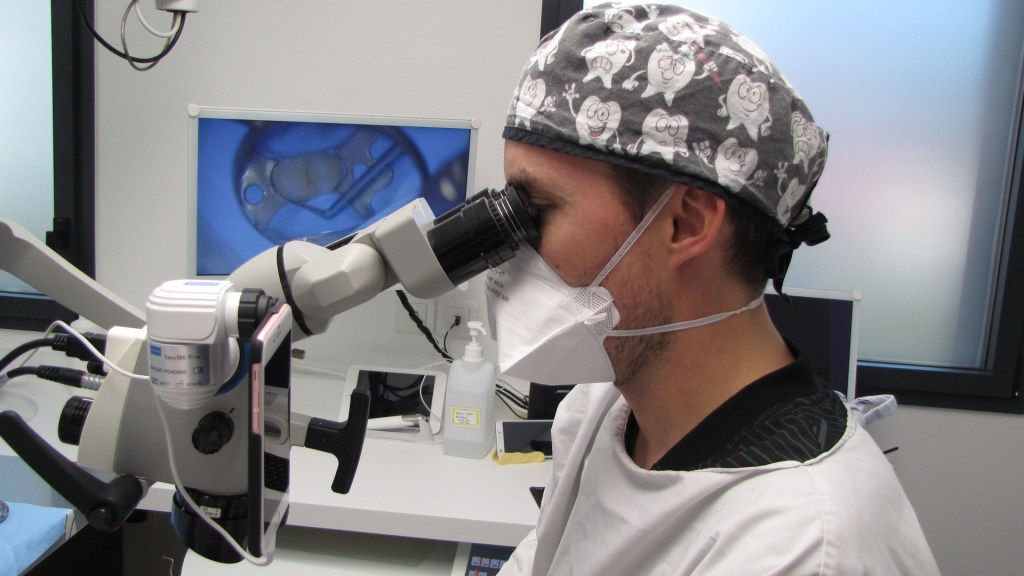

L’endodontie est une discipline complexe qui demande de la patiente, de la technicité et une grande précision. Certains traitements demandent également des compétences particulières. Aussi, bien voir ce qui extrêmement petit est indispensable, c’est pour cela que le docteur Florent BRIONNE est équipé d’un microscope opératoire.

Le docteur Florent BRIONNE reçoit des patients adressés par leur chirurgien-dentiste traitant pour effectuer ce type de traitements.